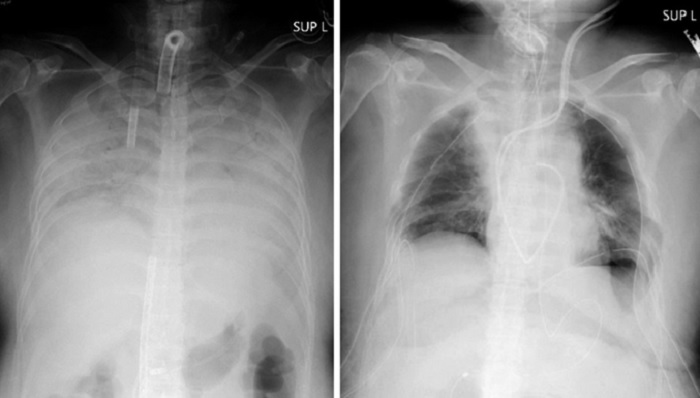

Ảnh chụp X-quang cho thấy phổi của một bệnh nhân COVID-19 trước và sau khi phẫu thuật cấy ghép.

Người phụ nữ sống ở miền tây Nhật Bản không có bệnh nền nhưng chức năng hô hấp của bà đã suy giảm nhanh chóng sau khi mắc COVID-19 vào cuối năm ngoái. Căn bệnh đã khiến cả hai phổi của bà co cứng lại và hầu hết các chức năng đều bị phá hủy. Khi các bác sĩ cho biết bà cần ghép phổi để sống sót, con trai và chồng bà đã quyết định hiến một phần phổi của họ. Họ đã được cảnh báo về những nguy cơ sức khỏe do giảm dung tích phổi.

Người phụ nữ nhập viện hôm 5/4 và được kết nối với một thiết bị tim phổi nhân tạo, được gọi là trao đổi oxy qua màng ngoài cơ thể (ECMO). Bà đã được ghép một phần phổi trái của chồng và một phần phổi phải của con trai hai ngày sau đó.